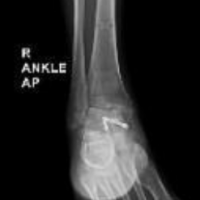

Clinical examination revealed no signs of radiculopathy, motor weakness, or restriction in neck mobility. However, a palpable small swelling (3 × 2 cm) was noted in the right supraclavicular region. The carotid artery was well palpated, and the swelling was lateral to the vascular bundle. Radiographs of the shoulder and neck revealed two broken K-wire fragments – one located in the right supraclavicular region and another posteriorly near the cervical spine (Fig. 1b and c). The shoulder radiograph showed a malunited lateral end clavicle fracture fixed with tension band wiring over two K-wires, both of which were broken distally. A non-contrast computed tomography (CT) scan of the neck was performed to delineate the exact position of the migrated wires (Fig. 2). The case was reviewed in a multidisciplinary team setting with input from an otorhinolaryngology expert. Routine pre-operative laboratory investigations were within normal limits, and the patient was planned for elective hardware removal.

Dissection was carefully performed in two anatomical planes around the trapezius muscle. The first K-wire fragment was identified anterior to the trapezius within the supraclavicular region. After blunt and sharp dissection through the platysma and fascia, the wire (8 cm length) was successfully retrieved (Fig. 3b). Dissection then continued posterior to the trapezius, where the second K-wire fragment (7 cm length) was located in the paraspinal musculature and removed without difficulty (Fig. 3c and d). In the same operative session, a separate incision was made over the acromion process to remove the tension band wiring from the acromioclavicular joint. The lateral clavicle fracture was found to be malunited, but as the patient was asymptomatic, no further intervention was performed. Both surgical sites were irrigated thoroughly and closed in layers. Post-operative radiographs confirmed complete removal of hardware (Fig. 4). The patient recovered uneventfully, with complete resolution of symptoms by the 1-month follow-up. At 3 months, he remained pain-free with a full, pain-free range of motion at the shoulder and cervical spine.